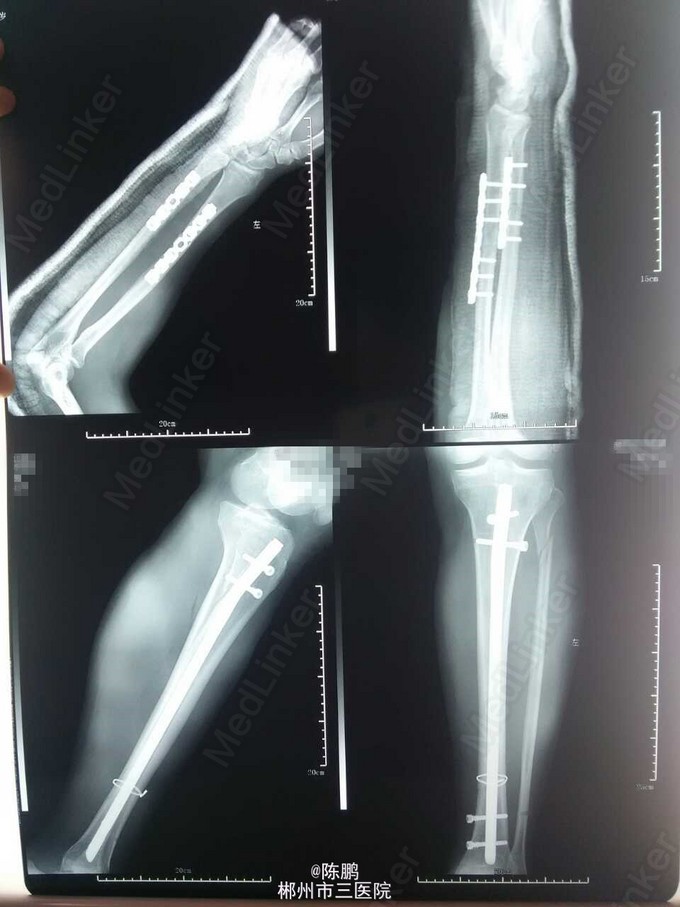

专科体查:左前臂明显肿胀,局部皮肤青紫,压痛,纵向叩击痛,可扪及明显骨擦感及闻及骨擦音,左前臂活动受限,左桡动脉搏动可,左小腿少肿胀,局部皮肤青紫,压痛,纵向叩击痛,中下1/3处可扪及明显骨擦感及闻及骨擦音,左小腿活动不能,左足背动脉搏动可,肢端血运感觉可,余肢体及脊柱未见异常。 辅查:x线示:左尺桡骨,左胫骨下段,左腓骨上段骨折

诊断:1.左尺桡骨骨折 2.左胫骨下段腓骨上段骨折 3.头部外伤:1)脑震荡 2)头皮挫裂伤 3)颅内血肿脑挫裂伤待查 行左胫骨下段骨折切开复位带锁钉内固定及左尺桡骨下段骨折切开复位,钢板内固定术